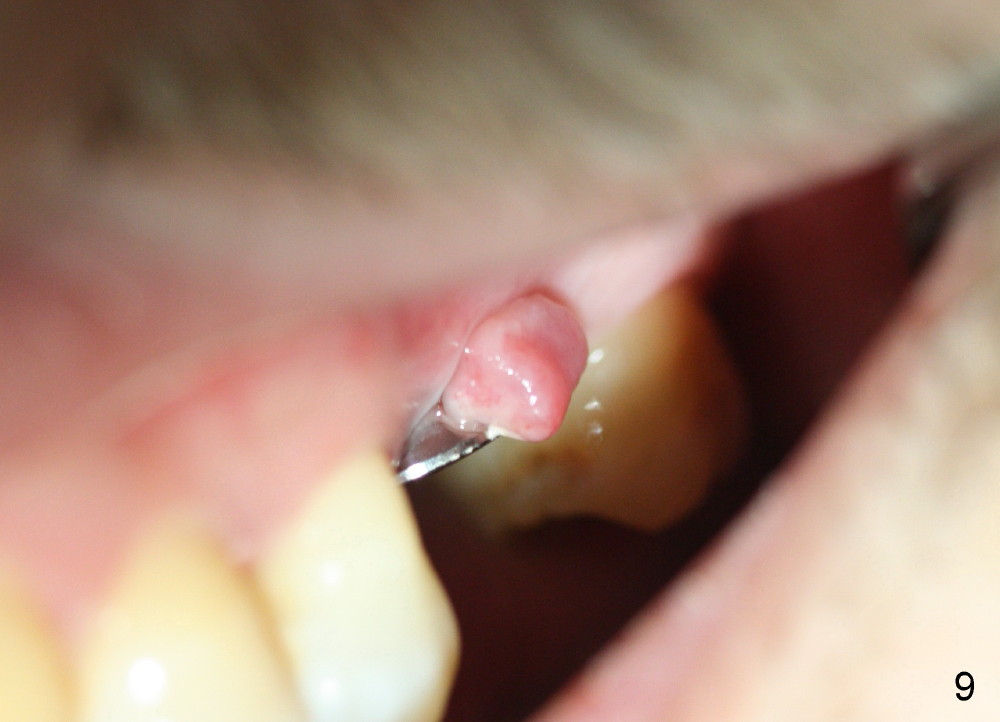

A 45-year-old man has lost the tooth #14 for a while (Fig.1); bone height is 5.4 mm. An extra wide and short implant is planned. Torus palatinus is large, suggesting that bone density should be high. A 6 mm tissue punch is chosen, but it is placed more palatal. If it were placed in the middle of the ridge, there would be no buccal keratinized gingiva (incision may avoid this issue). Additionally, the buccal portion of punch is made incomplete so that there is pedicle on the buccal side when the flap is raised (Fig.4,8: F). It is expected that the excess portion of keratinized tissue will form thick gingiva buccally. Osteotomy proves that bone is dense (Fig.2 (4.5x11 mm tap). Typical sinus lift is finished with placement of 6.4x6 mm (extra wide) bone-level implant (Fig.3, >55 Ncm). Following further torque, Fig.4 shows that the implant (I) is sub-gingival (<). Bitewings are taken to confirm that the implant plateau is at the crestal level (Fig.5,6 ^). PA shows sinus lift (Fig.7 *). The lingual aspect of the implant and healing abutment (H) is further bone grafted and covered by collagen dressing (Fig.8 *). The wound is protected with perio dressing. When the latter dislodges 7 days postop, the collagen dressing and bone graft are lost as well (Fig.10), while the buccal flap remains vital (Fig.9). The lingual exposed plateau should be able to heal normal. The collagen dressing should have been fixed in place by suture or as simple as a dental floss. There is mild nasal hemorrhage 1-2 days postop, possibly related to sinus membrane perforation and inability of Collagen Dressing to cover the perforation and contain the bone graft. When the patient returns for #9 implant placement in 3 weeks postop, the buccal flap reduces in size (Fig.11 *), while the palatal wound has healed with minimal exposure of the implant (Fig.12). Sinus graft remains in place 3 months postop (Fig.13); the buccal flap appears to have incorporated into a part of the gingiva (Fig.14). The bone density of the sinus lift appears to increase 10 days later when an abutment is placed (Fig.15 *). Although oral hygiene is pristine, there is apparent crestal bone resorption 12 months (Fig.16) and 20 months (Fig.17) post cementation, probably due to unfavorable crown/implant ratio and bruxism as well as pre-implantation bone loss (Fig.18,19). In contrast, an immediate implant in the same patient avoids pre- or post-implantation bone loss. In fact both the soft (Fig.20) and hard (Fig.21) tissues remain healthy 2 years 8 months post cementation. The sinus lift remains 3 years 8 months post cementation (Fig.22), while the crestal bone loss persists. The patients keeps complains of food impaction distal associated with bad smell 4 years 1 month post cementation. In fact the distal proximal contact is within normal limit. The bad smell is probably due to crestal bone loss (Fig.23 (pan), 24 (CT) *) and periimplantitis. Bone graft, PRF and Cytoplast membrane will be needed and fixed in place with long healing screw. When the patient returns for crown redo, he also reveals floss related gingival hemorrhage. There is pain associated with palatal sulcus probing with light gingiva erythema. Review of CT coronal section shows possible palatal (Fig.25 P) bone loss (*).